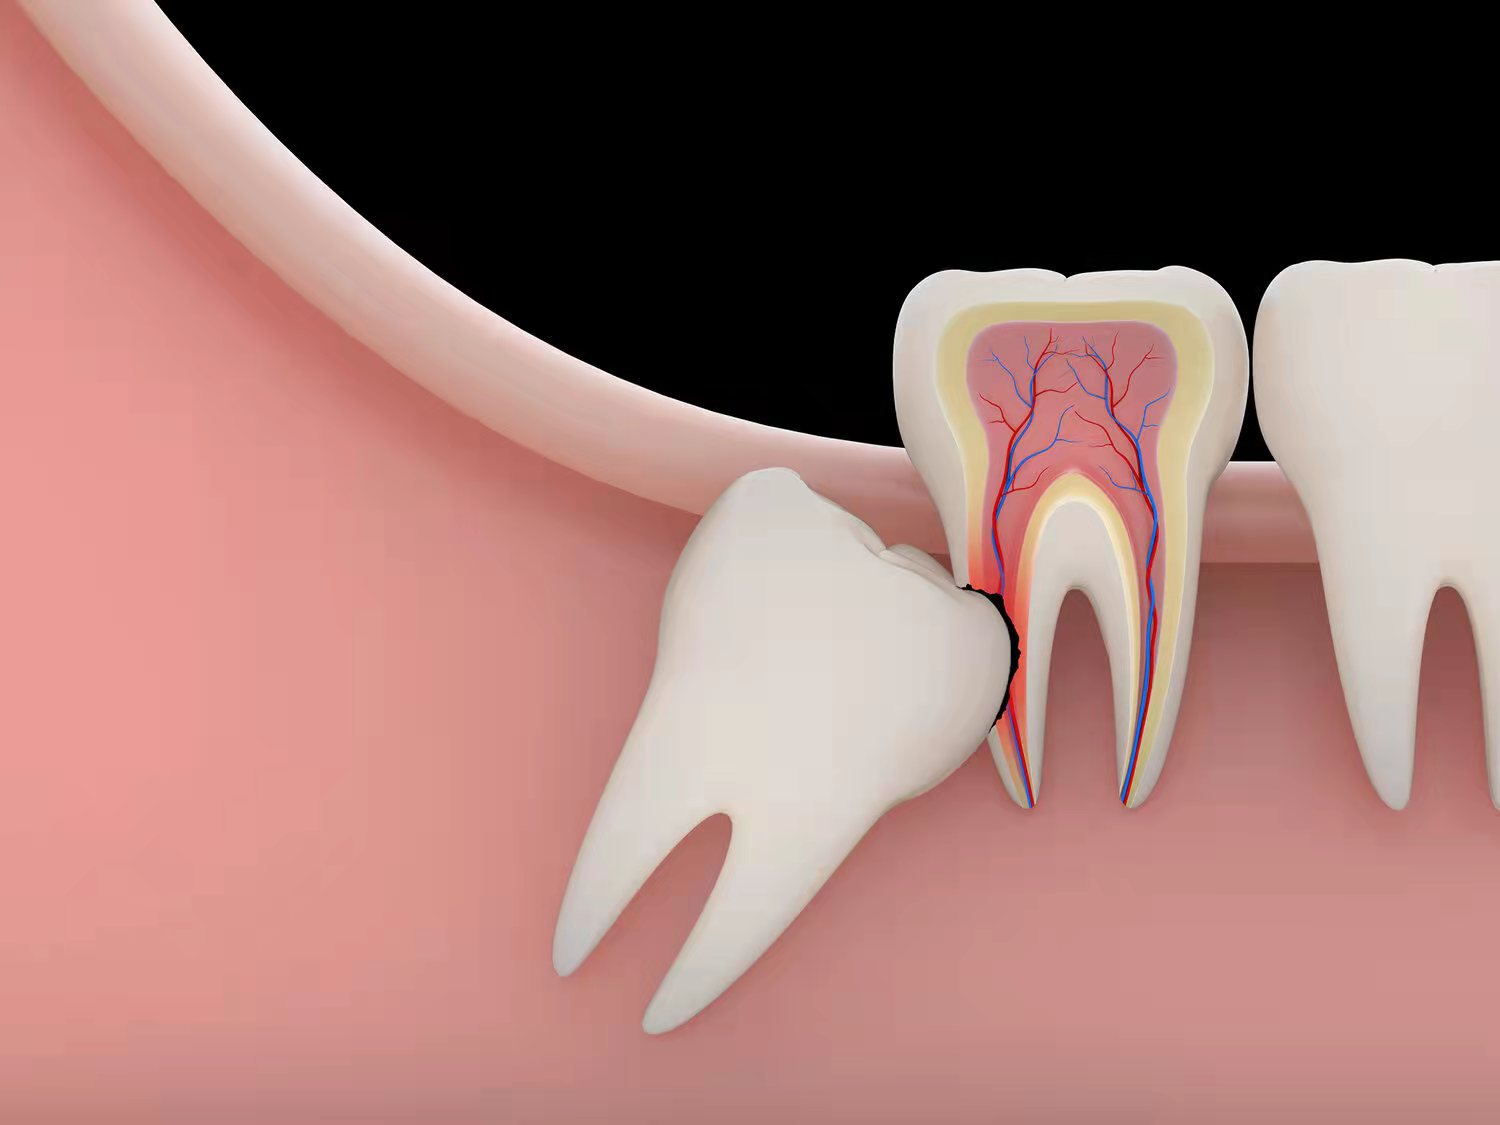

③影响其他牙齿

智齿在出现过程中,经常会影响到周围的牙齿,甚至会把周围本来好好的牙齿给顶坏了,这个时候也必须拔除。

②反复发炎

大部分去拔智齿的人,都是因为被反反复复的炎症折磨得痛苦难耐。当牙齿和牙龈缝隙里经常有食物残渣时,就很难清洁。长期如此,就会诱发冠周炎。炎症往往比较难控制,肿胀和疼痛让人叫苦不迭,这时候就必须去拔了。[2]